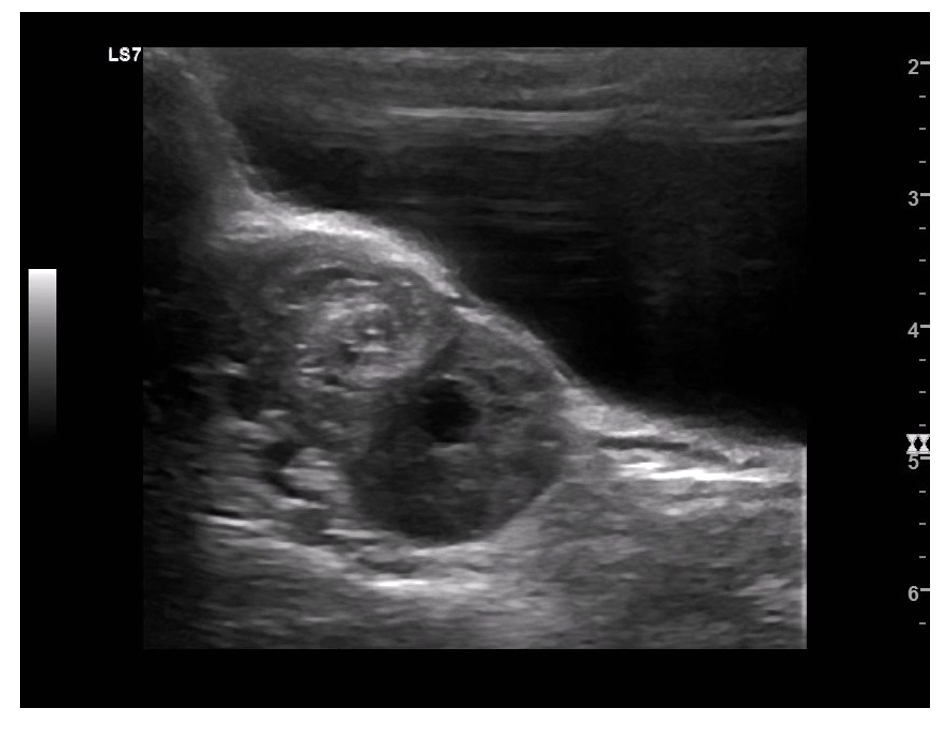

Ultrasound appearance of cysts:

Simple cysts: thin-walled, anechoic, no septations.

Complex cysts: multilocular, thickened walls, mixed solid/cystic components.

Common US findings:

Enlarged ovary.

Midline positioning of ovary.

Peripheral displacement of follicles.

Pelvic free fluid.

Heterogeneous ovarian stroma.

Key ultrasound finding:

“Whirlpool sign” (twisted vascular pedicle) (sensitivity ~65%, specificity ~91% (Garde et al., 2022))